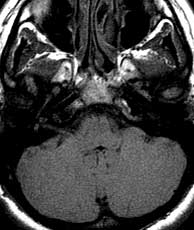

T1 axials pre gad

Findings:

Negative. The right labyrinth is normal pre-gad.